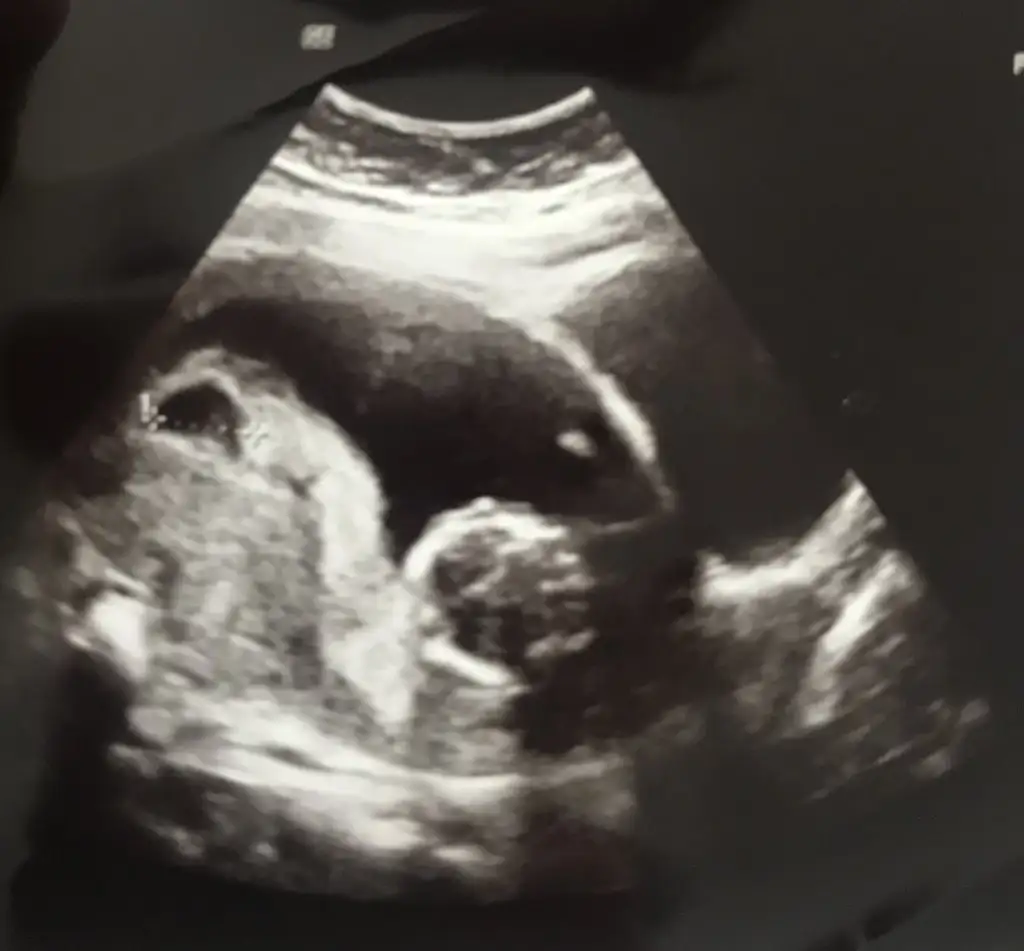

Ayin 18 randevum bende valla korkuyorum acikcasi gitmek istemiyor bir tarafim rabbim hayirlisini nasip etsin diye bol bol dua ediyorum